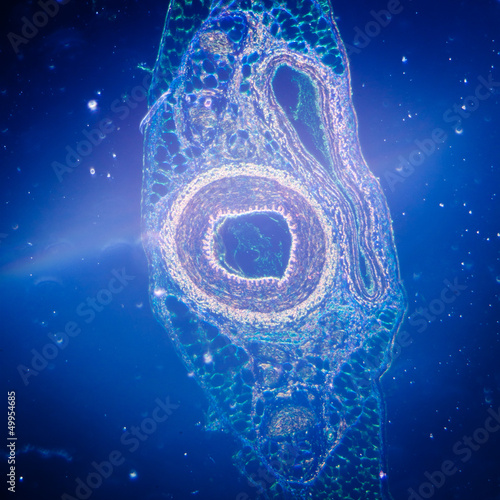

Mikrofotografi - Plakater, Poster, Billeder på lærred